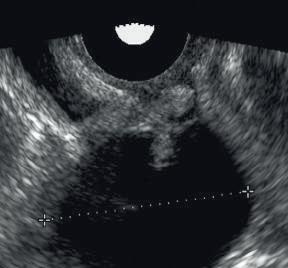

in what is actually a simple ovarian cyst.

FIG. 1.30 Multipath Artifact. (A) Mirror image of the uterus is created by reflection of sound from an interface produced by gas in the rectum. (B) Echoes reflected from the wall of an ovarian cyst create complex echo paths that delay return of echoes to the transducer. In both examples, the longer path of the reflected sound results in the display of echoes at a greater depth than they should normally appear. In (A) this results in an artifactual image of the uterus appearing in the location of the rectum. In (B) the effect is more subtle and more likely to cause misdiagnosis because the artifact suggests a mural nodule